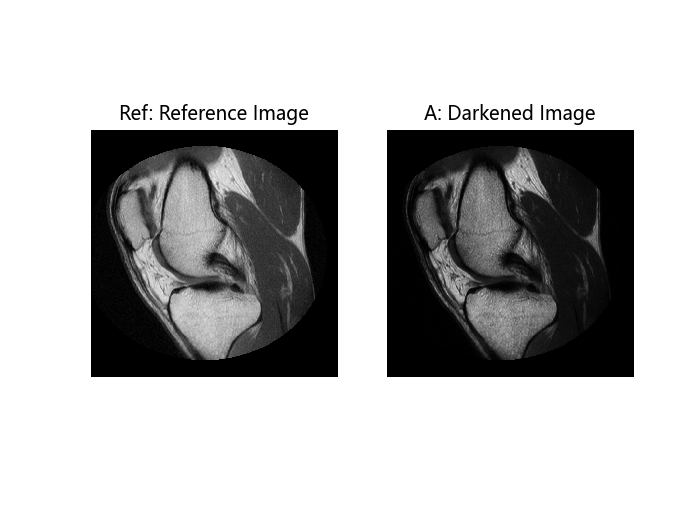

将参考图像 Ref 变暗,以创建一个可以用于直方图匹配操作的图像 A。

查看参考图像 Ref 和变暗后的图像 A。注意它们具有相同数量的离散代码值,但整体亮度不同。

subplot(1, 2, 1)

imshow(Ref)

title("Ref: Reference Image")

subplot(1, 2, 2)

imshow(A)

title("A: Darkened Image");